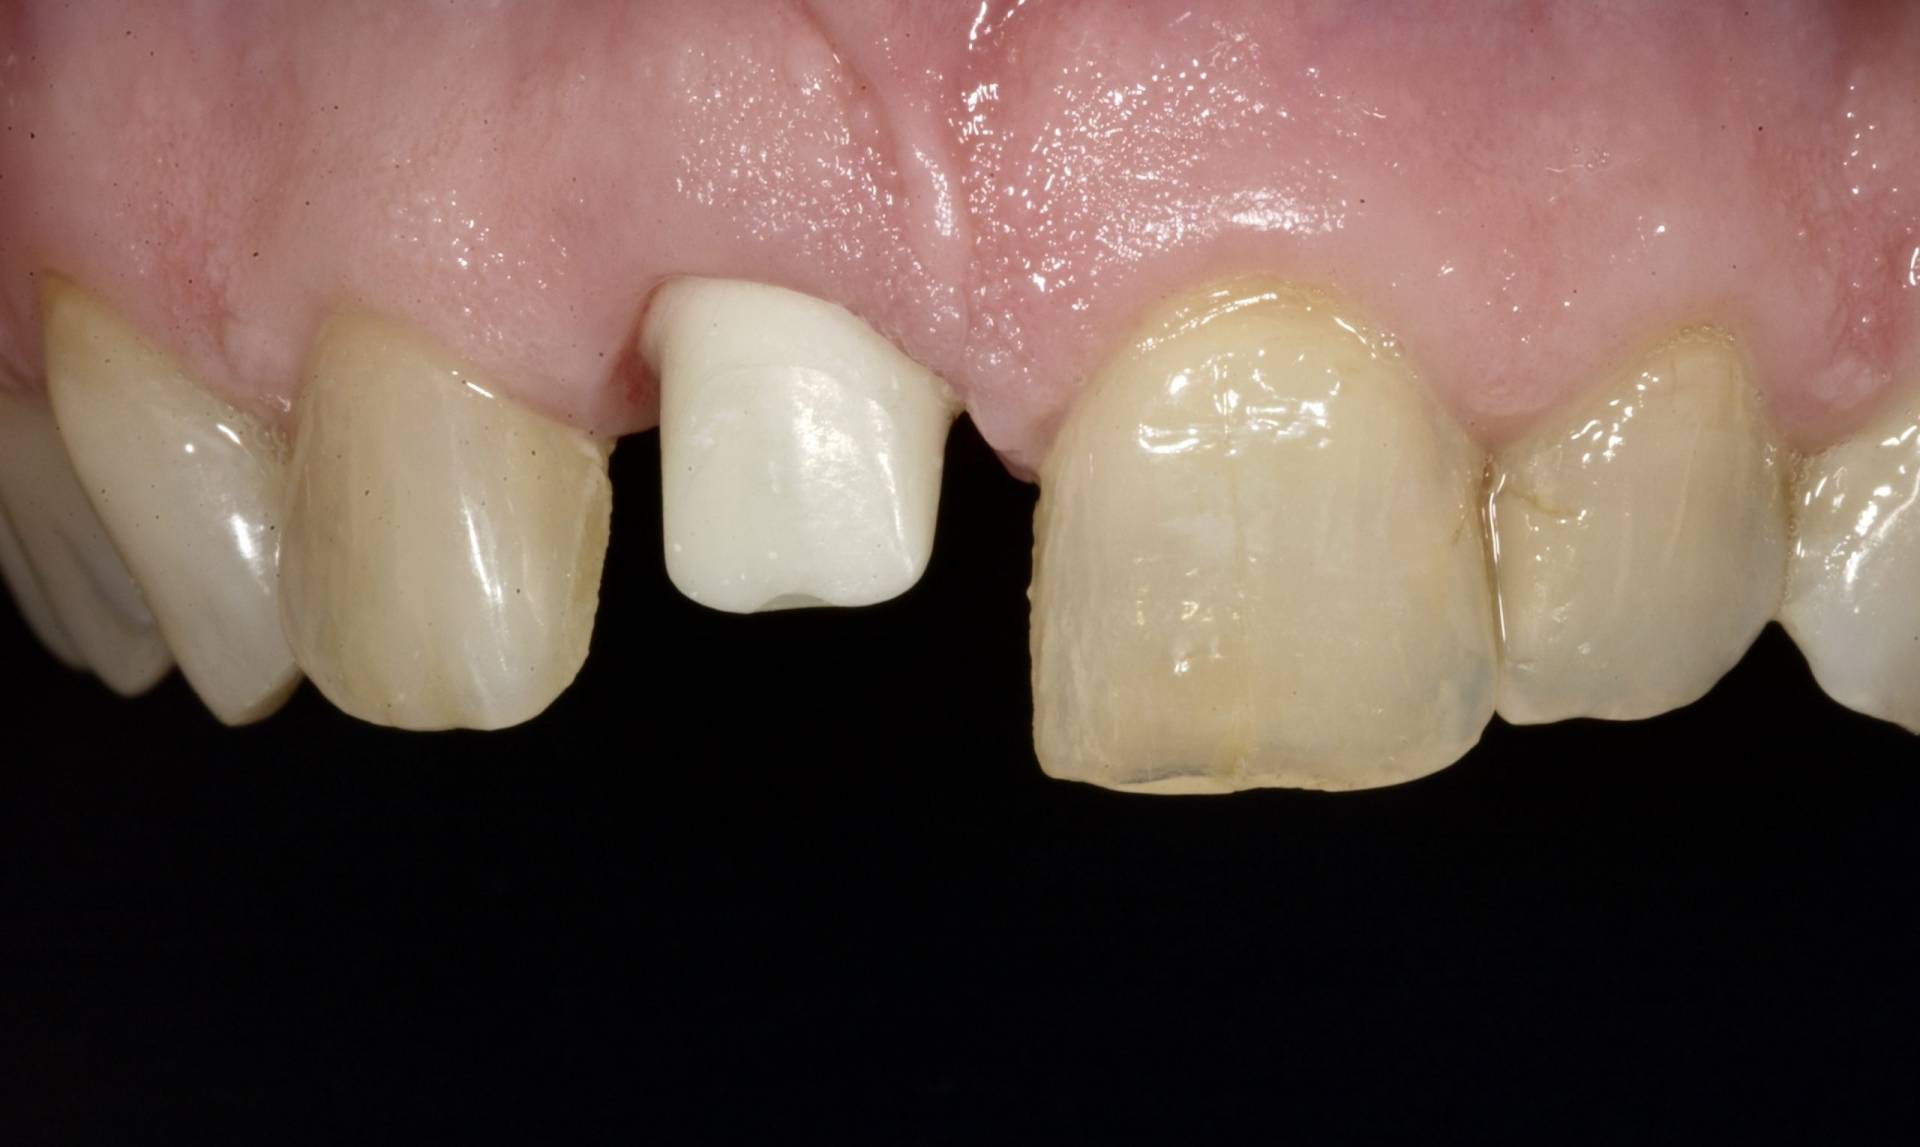

Ein Implantat trägt nicht nur zur Wiederherstellung von Kaufunktion und Ästhetik bei, sondern schützt auch den Kieferknochen vor Abbauprozessen, die nach Zahnverlust auftreten können. Voraussetzung für den langfristigen Erfolg ist eine sorgfältige Planung unter Berücksichtigung von Knochenangebot, Weichgewebe, Funktion und individueller Belastung.

Mithilfe moderner Diagnostik, mikrochirurgischer Techniken und gewebeschonender Verfahren schaffen wir optimale Voraussetzungen für eine sichere Einheilung. Bei Bedarf werden knochenaufbauende Maßnahmen und biologische Regenerationskonzepte integriert, um auch in anspruchsvollen Situationen stabile Ergebnisse zu erzielen.